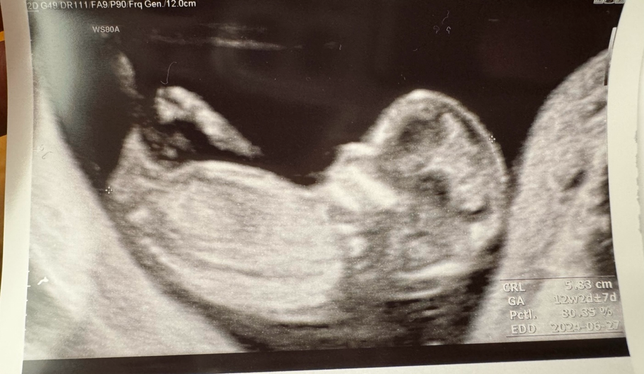

- 기타 육아상담육아Q. 인터넷에 유명한 각도법 정확도가 높을까요??카페에서 보면 각도법으로 성별을 알수있다고 하는데정확도가 높을까요??어떻게 보는지 몰라 설명부탁드립니다.사진으로 확인가능할까요~